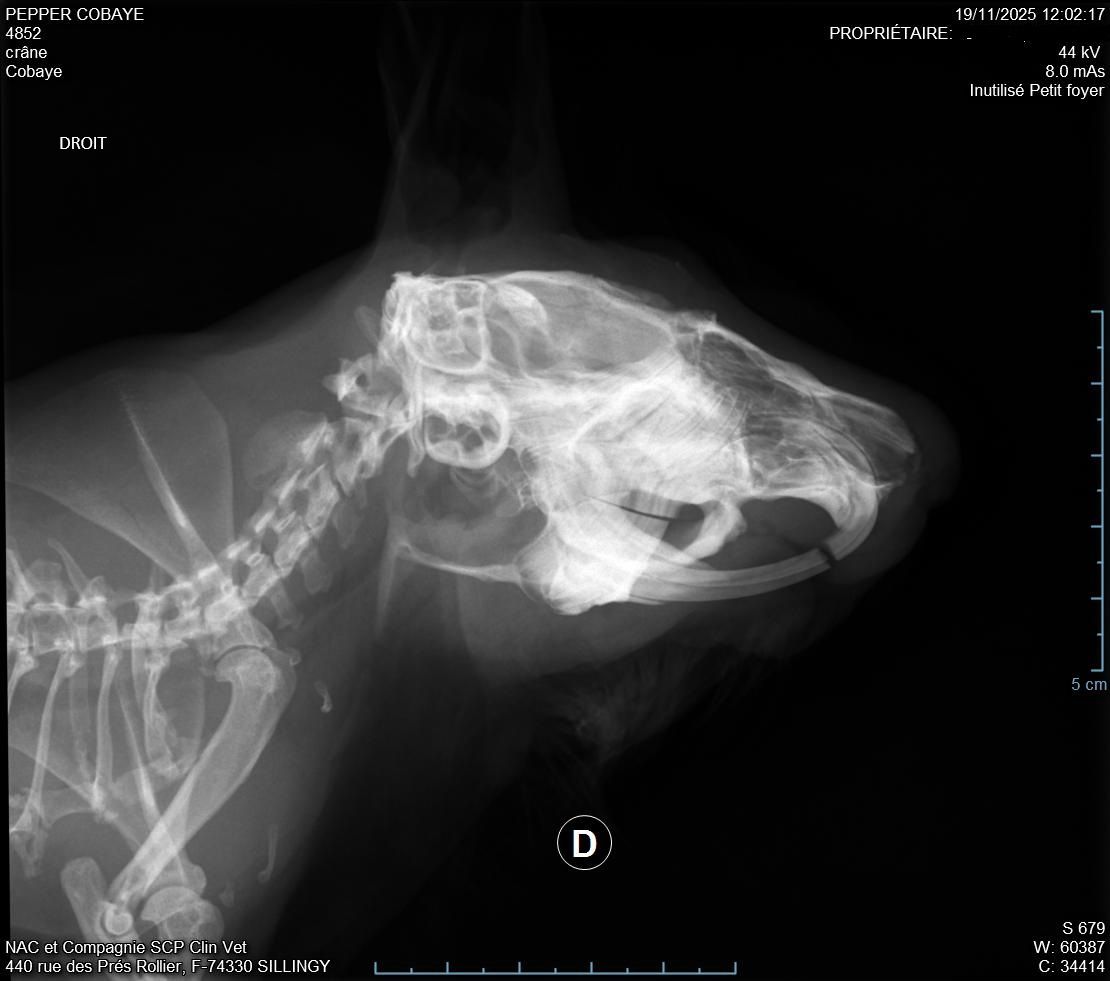

Descendu à 987g donc pas trop bougé depuis la semaine d'avant. La plaie était atone et moins belle que la semaine d'avant (pronostic pas très bon), il a fait des radios pour voir s'il n'y avait pas un problème avec ses dents mais il n'a rien vu, si pas d'amélioration il n'a pas d'autre solution. Nous somme donc repartis pour 10 jours avec un 2eme antibio en continuant le Corylap, Flagyl 125mg/ml 1ml 2x/jour + Contramal 2 à 4 gouttes 2x/jour et toujours Métacam avec le même dosage + Elugel 2x/jour sur la plaie. Changement de gavage pour Critical Care herbivore.

Jour après jour, malgré le gavage son poids n'arrive pas à se stabiliser, il fait grincer ses dents pour ne pas qu'elles poussent de trop et elles sont maintenant en biais alors qu'elles étaient très belles avant.